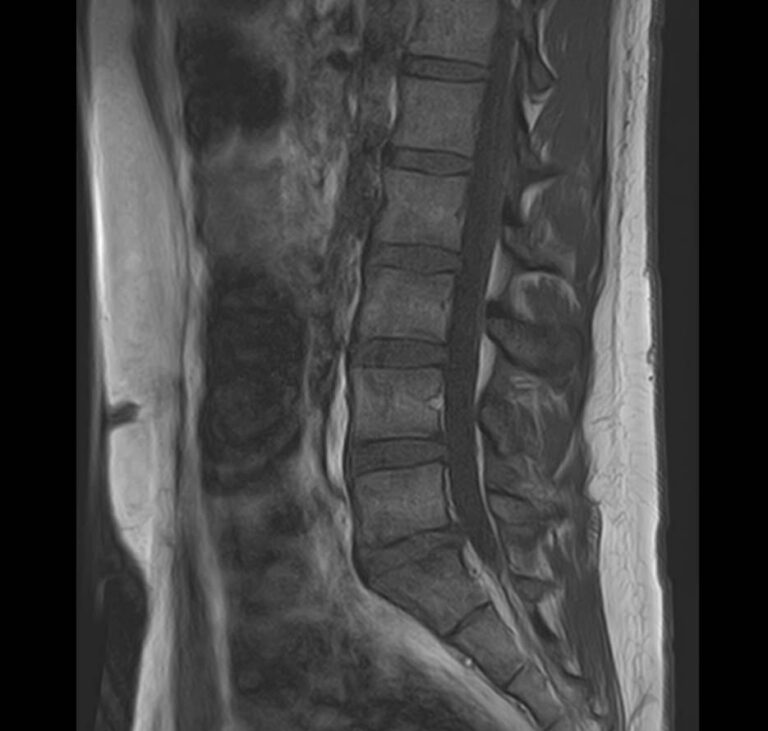

При сочетанном поражении этих анатомических областей целесообразно проведение комплексной МРТ, включающей обследование пояснично-крестцового отдела позвоночника и коленных суставов.

Магнитно-резонансная томография является высокоинформативным методом выявления причин возникновения заболеваний позвоночного столба и суставов. В клинике «Доступная медицина» диагностика осуществляется на новейшем высокопольном томографе закрытого типа TOSHIBA VANTAGE TITAN 1,5 Тесла, обеспечивающем высочайшее качество изображений исследуемой зоны.

Томограф позволяет детально визуализировать состояние всех анатомических структур позвоночного столба на исследуемом уровне, костные структуры колена и окружающие мягкие ткани данных анатомических областей, включая мышцы, связки, нервные сплетение, сосуды.